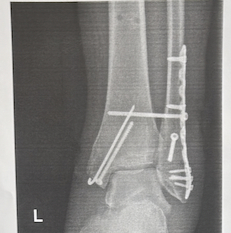

Отпуск пошёл не по плану и завершился двойным переломом лодыжки с подвыпердом подвывихом и смещением. Спасибо врачам больницы им. Юдина за то, что собрали ногу обратно и аккуратные швы! В ноге теперь редкоземельные металлы и мерзопакостная штука под названием фиксирующий винт (для восстановления разрыва синдесмоза), из-за которого на 2,5 месяца на ногу наступать категорически нельзя.

Морально еще не прошел все стадии принятия неизбежного (об ограничении подвижности на 2,5 месяца), нахожусь сразу на стадии злость и депрессия. Особенно, когда узнал, что вместо болта могут ставить своего рода кнопки, между которыми натягиваются нити и не нужно ждать 2,5 месяца.